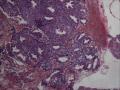

宫内刮出物,怀疑宫外孕?能见到滋养叶细胞吗?

宫外孕

宫内容物

未见绒毛。

未见滋养叶细胞

只见蜕膜样变。

这些细胞不能说完全不是,如果有剩余组织,建议再取材找找,这种情形感觉还是个流产。

可疑中间型滋养叶细胞,考虑宫内流产。

高倍视野中的异型、多形细胞,伴有退变、胞质空亮均是滋养细胞。